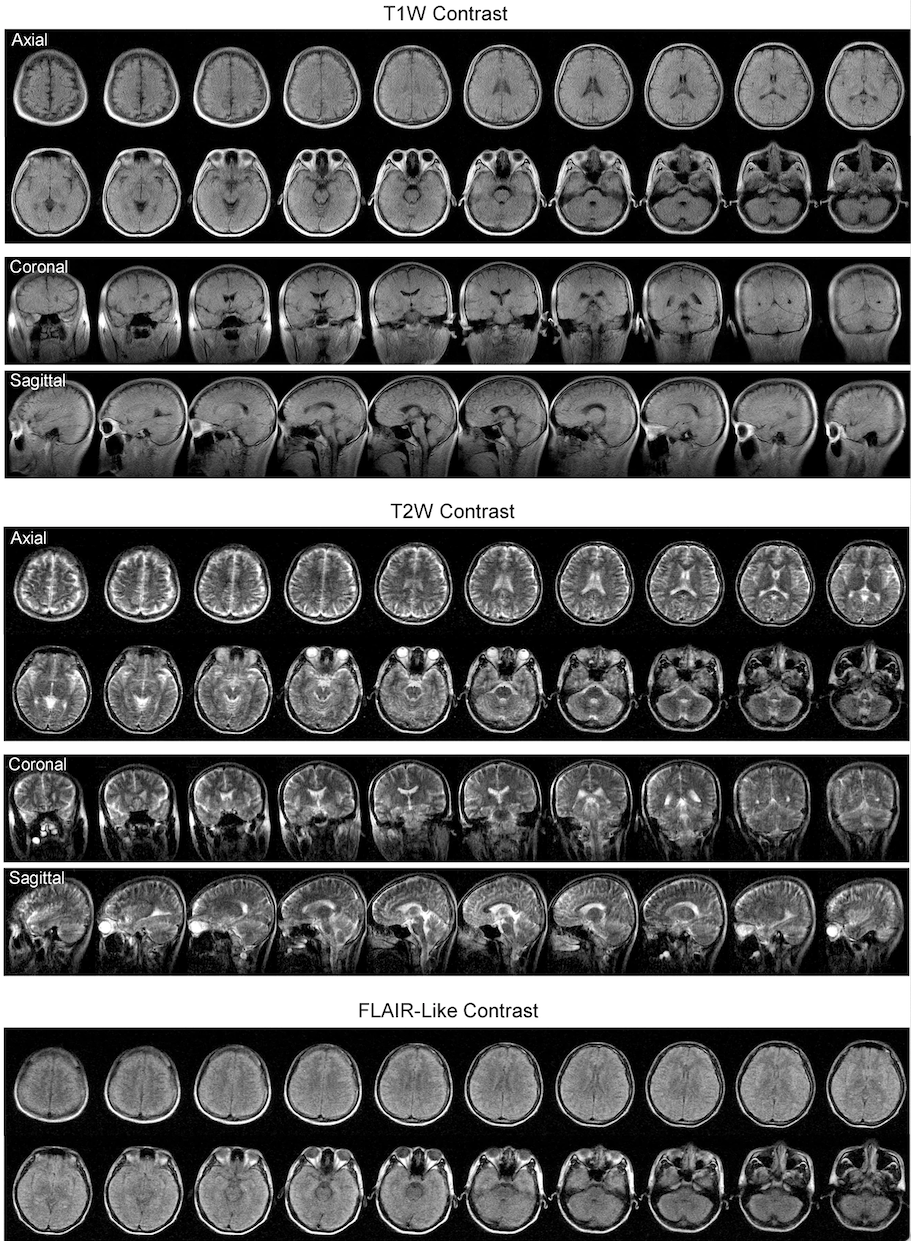

Researchers from the University of Hong Kong (HKU) have successfully developed a new magnetic resonance imaging (MRI) technology, the ultralow field (ULF) 0.055 Tesla brain MRI, which can operate from a standard AC wall power outlet and requires neither radiofrequency nor magnetic shielding room.